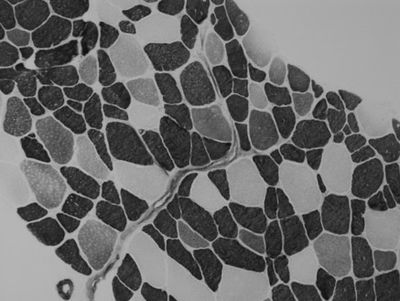

Determining Skeletal Muscle Fiber Type in Regenerating Muscle after Injury Induced by Electrical Stimulation of the Vastus Lateralis

The purpose of this study was to characterize injured skeletal muscle fibers regenerating post-injury. Based on discoveries in previous research studying the mechanisms of muscle regeneration, we wanted to look further into the interactions between the cells involved in this process. One study done by Abigail Mackey and colleagues (2011) observed that after induced injury, multiple muscle fiber membranes on serial sections of human gastrocnemius muscle biopsies encroached into one fiber, fusing what was observed as two or more fibers in other locations on the biopsy. We hypothesized that only those fibers which are type II myosin are effected by the electrical stimulation, exhibiting signs of regeneration indicated by fusing and the presence of embryonic and/or neonatal myosin. However, a second hypothesis stated that if a fiber expresses immature myosin, ATPase stains cannot be relied on to determine fiber type. To test the hypotheses, we analyzed serial sections from skeletal muscle biopsies collected following electrically induced eccentric contractions in the vastus lateralis muscle. Methods included imaging of the prepared slides and characterization of the fibers by measuring the size and length of regenerating fibers and determining their myosin type. The results, which showed that none of the type I fibers and most of the type II fibers expressed neonatal myosin, led us to conclude that only type II fibers were affected by the electrical stimulation. We were also able to confirm that the ATPase stain analysis could accurately determine fiber type for those positive for neonatal myosin, but not those expressing embryonic myosin.

Højfeldt, Grith, Trent Sorenson, Alana Gonzales, Michael Kjaer, Jesper L Andersen, Abigail L Mackey (2023). “Fusion of myofibre branches is a physiological feature of healthy human skeletal muscle regeneration,” Skeletal Muscle, vol. 13, 13.